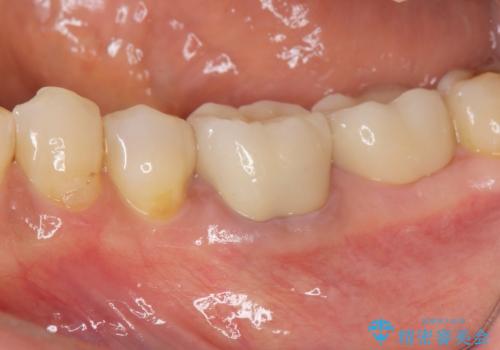

- 前歯の付近、歯ぐきを押すと違和感を感じその改善を求めて来院されました。

X線検査の結果、失活(感染根管)であることが判明したので、感染根管治療後セラミック補綴を計画します。